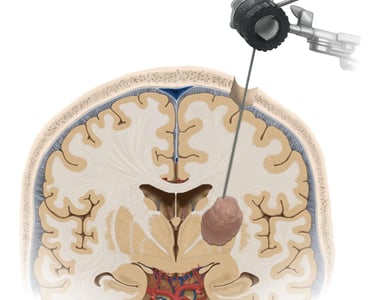

Tumores cerebrales y espinales

Biopsias cerebrales